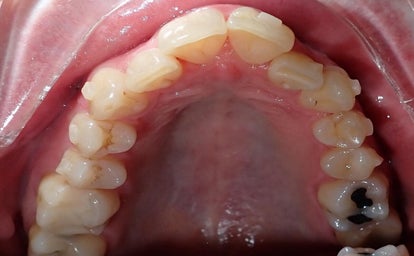

Klinisch voorbeeld :

Klassieke blokjes bij een volwassen patiënt. Er is wat tand slijtage te zien, voornamelijk ter hoogte van de ondersnijtanden. In overleg met zijn tandarts werd er besloten om eerst de positie van de tanden te corrigeren alvorens men begint met de andere dentale behandelingen.